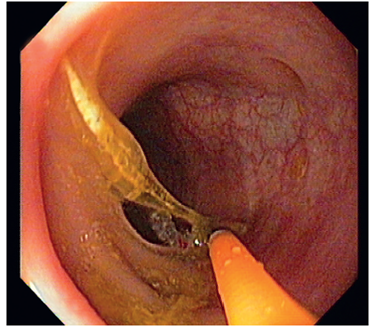

En las siguientes 24 horas, se practicó una endoscopia digestiva baja y se extrajo una espina de pescado de 3,8 cm de longitud, sin complicaciones inmediatas (figuras 2 y 3).